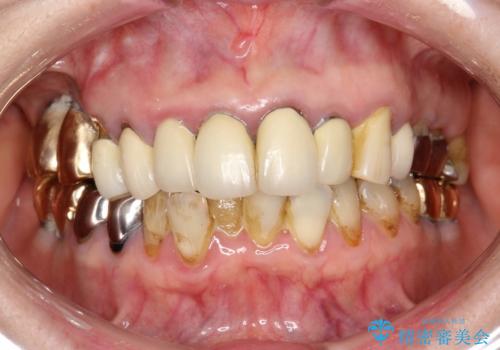

前歯の低クオリティな治療の実態 妥協無い治療で根本からやり治す

・虫歯がとりきれていない

・接触部分がガタガタで適合の悪い金属

・全く無菌の努力がされていない根管治療

など、いい加減な治療は「治療」ではなく、むしろ医原性に歯の寿命を短くします。

最もよくないのは、クオリティの低い治療を何度も繰り返すことです。

時間をかけ、妥協なく治療を行い、今後の再治療の可能性を極力少なくするために、

費用や時間といった労力がかかってしまうのは当然のことです。